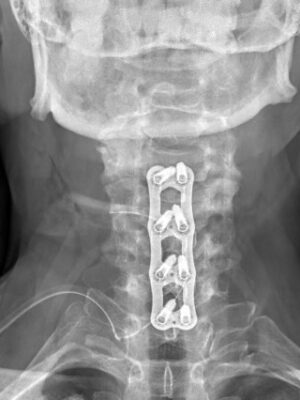

Krční páteř

Krční páteř operujeme nejčastěji z předního přístupu. Příčným řezem v tzv čárách štěpitelnosti kůže (vráskách) se dostaneme k postiženému segmentu páteře. Po odstranění meziobratlové ploténky a osteofytů, které utlačovaly nervové struktury nahradíme vyplníme meziobratlový prostor implantátem vyplněným kostním štěpem odebraným z lopaty kosti kyčelní a obratlová těla fixujeme speciální krční dlahou.

V případech víceetážového postižení krční páteře volíme operační přístup zadní.